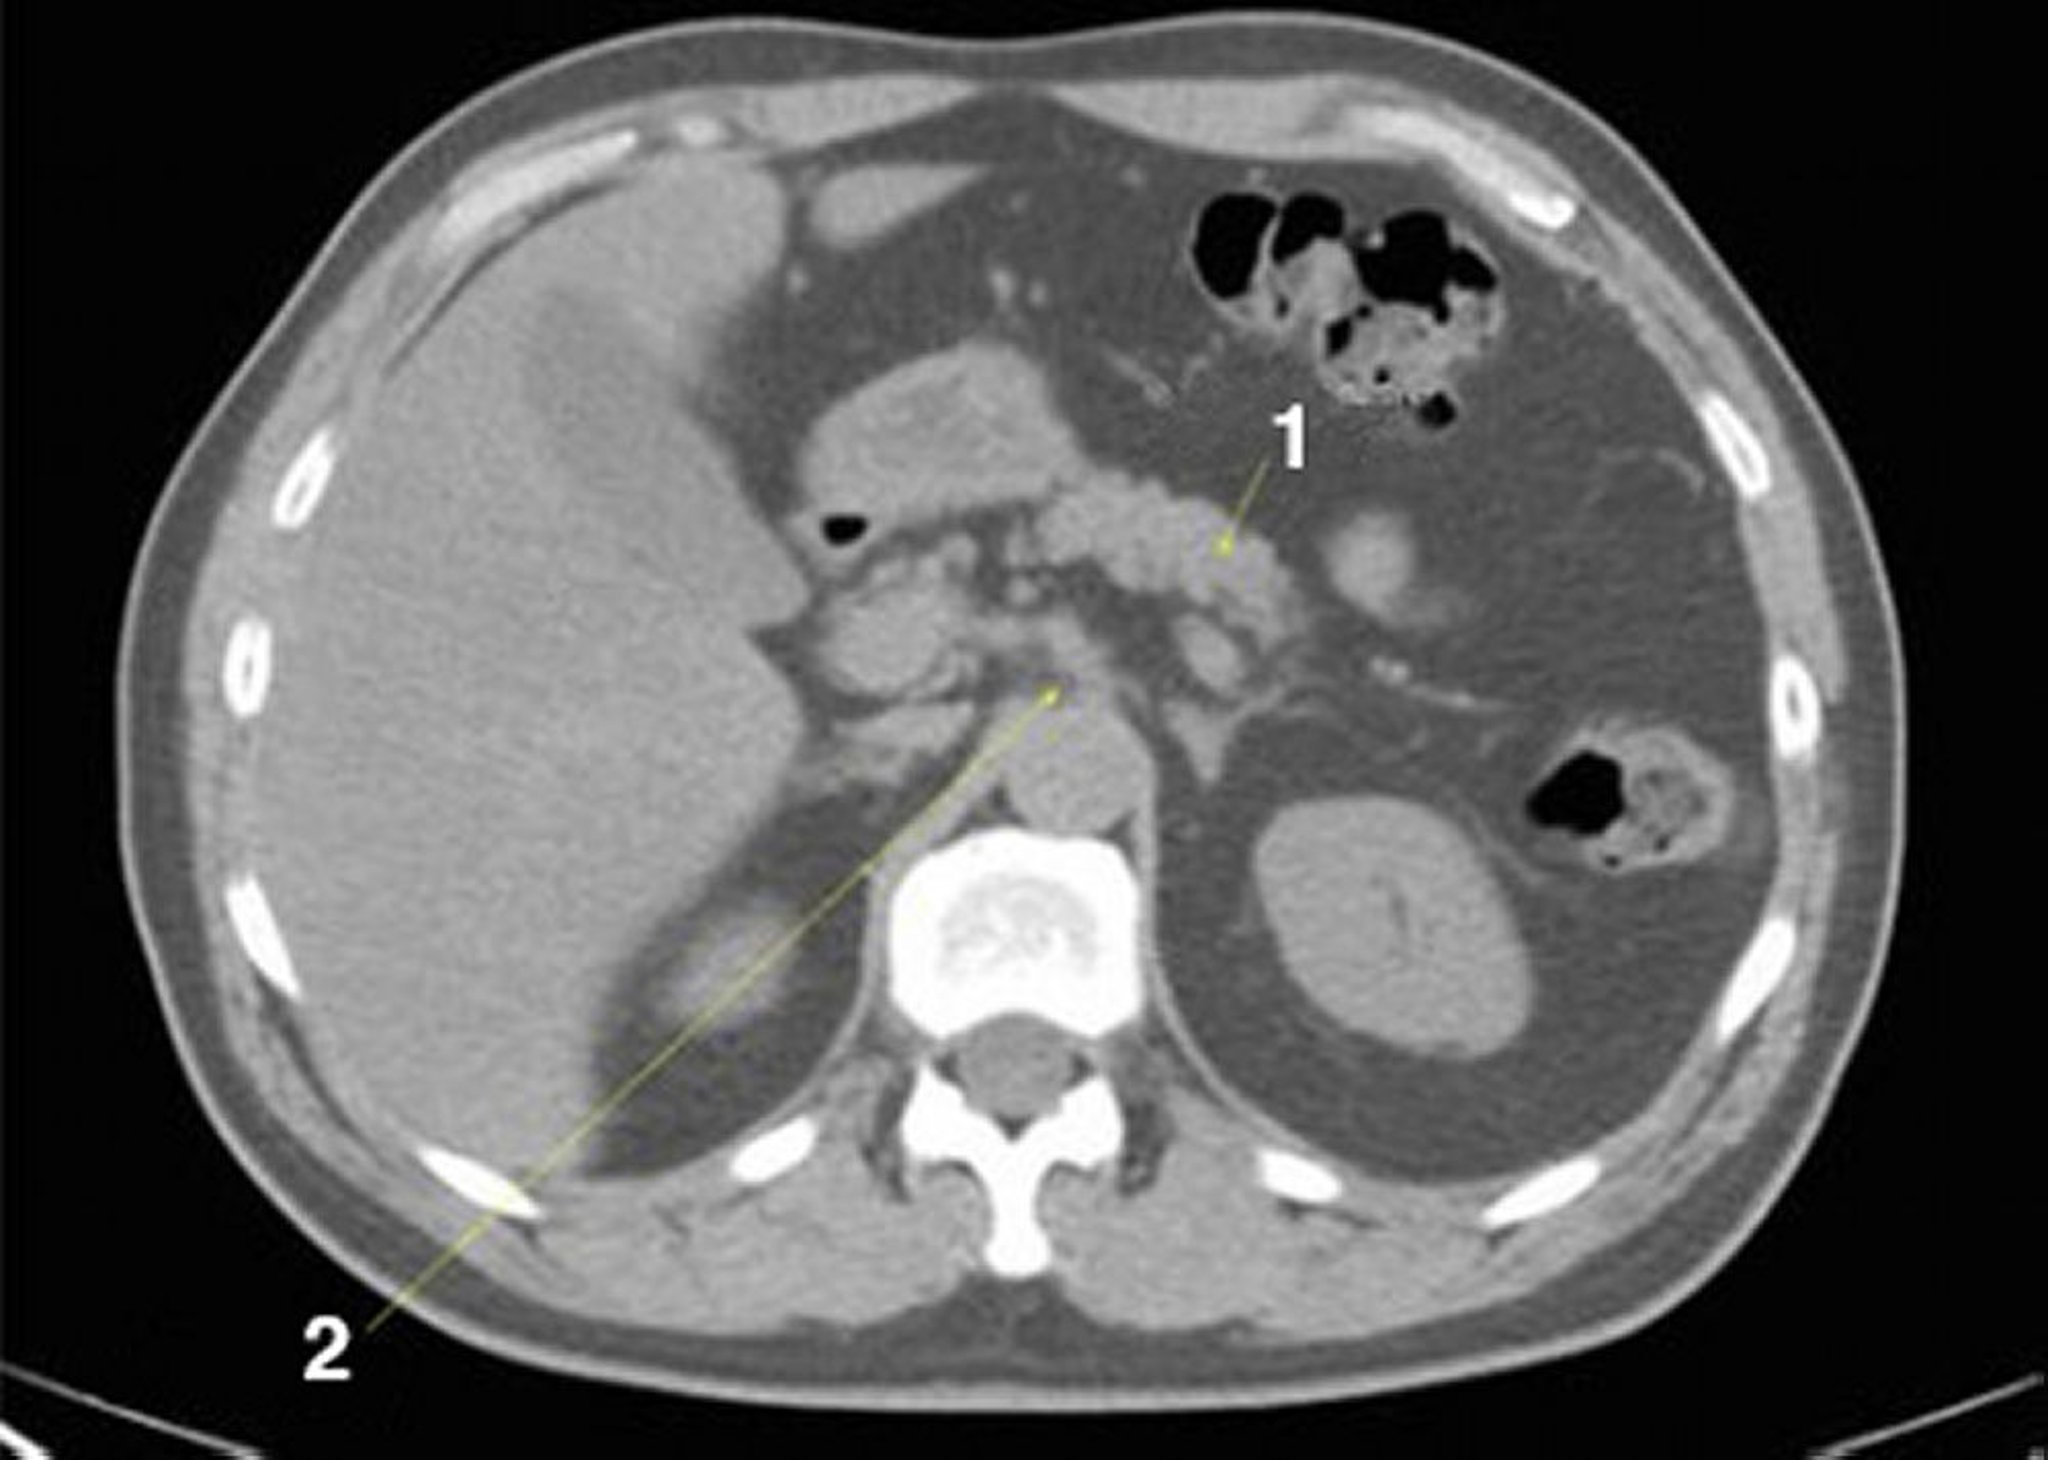

CT-Scan von Abdomen und Becken mit normaler Anatomie ohne Kontrastmittel (Folie 9)

1 = Pankreas; 2 = zöliakale Achse.